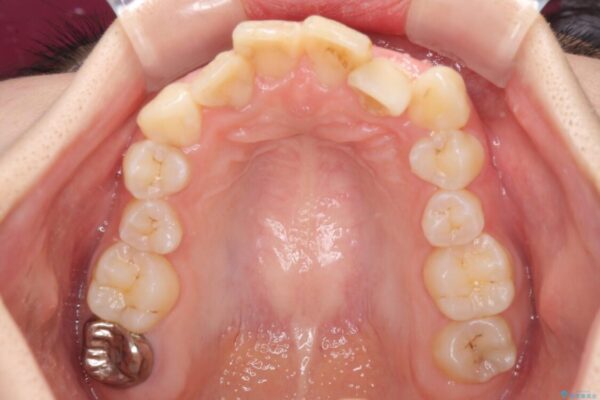

内側に倒れ込んだ歯や下の前歯が隠れてしまうほどの咬み合わせを改善したいとのことで来院された患者様です。

下顎の叢生を解消するために抜歯が必要であり、奥歯の咬み合わせや口元の印象から、上顎も同様に抜歯と判断し、上下左右の第1小臼歯4本抜歯してワイヤー装置にて矯正治療を行うこととしました。

治療前

• デコボコと深い咬み合わせ ワイヤー装置での抜歯矯正 治療前画像